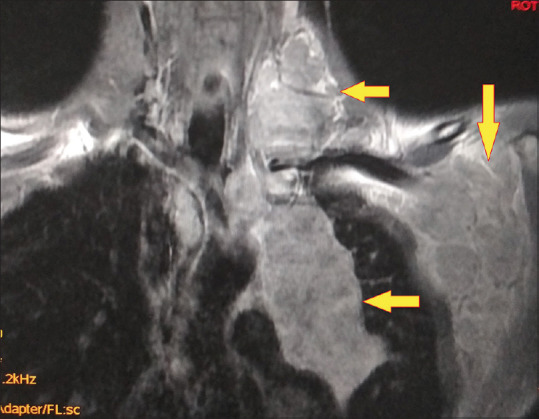

霍奇金淋巴瘤合并结核病是一种极为罕见的临床病例,由于临床表现相似,因此很难处理。本病例报告描述了一名 44 岁男性患者的相同情况,该患者被诊断为科氏淋巴瘤,并在脊柱活检和培养结果证实的基础上开始接受抗结核治疗。尽管接受了结核病治疗,但患者的临床症状仍在恶化。因此,对患者进行了进一步检查,包括纵隔镜检查和支气管内超声检查。从下颈部和纵隔内的聚集性肿块中提取的活检样本显示为结节性硬化型霍奇金淋巴瘤。在接受化疗和放疗以及抗结核治疗后,患者的病情有了明显好转。

Concomitant Hodgkin's lymphoma with tuberculosis is an exceedingly rare clinical scenario and a condition that is difficult to manage due to similar clinical presentation. This case report describes the same in a 44-year-old male patient diagnosed with Koch's and initiated on antituberculosis therapy, based on confirmation of findings from the spine biopsy and culture. The patient's clinical condition worsened despite being on treatment for tuberculosis. Hence, further work up of the patient was done which included mediastinoscopy and endobronchial ultrasound. Biopsy samples from a conglomerate mass in the lower cervical region and mediastinum revealed Hodgkin's lymphoma of the nodular sclerosis type. This time, the patient showed significant improvement following treatment with chemotherapy and radiotherapy along with antituberculosis therapy.